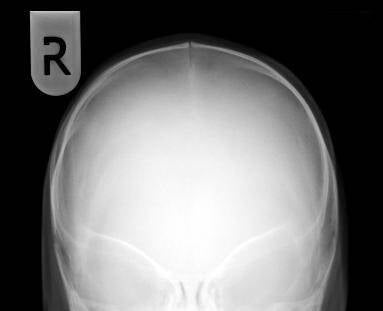

Allereerst de foto's van begin juni. Heel duidelijk kun je zien dat de zogenaamde pijlnaad gesloten is en de bootvorm van de schedel.

De volgende foto's zijn van de eerste controle na drie weken en 4 dagen. Hier kun je goed de veren zien zitten. Ik heb het contrast van de eerste foto iets vergroot zodat je duidelijk zaagsnedes kunt zien zitten en hoever deze al wijken door druk van de veren. Ook kun je al goed zien hoe de bootvorm is afgenomen aan de achterkant.